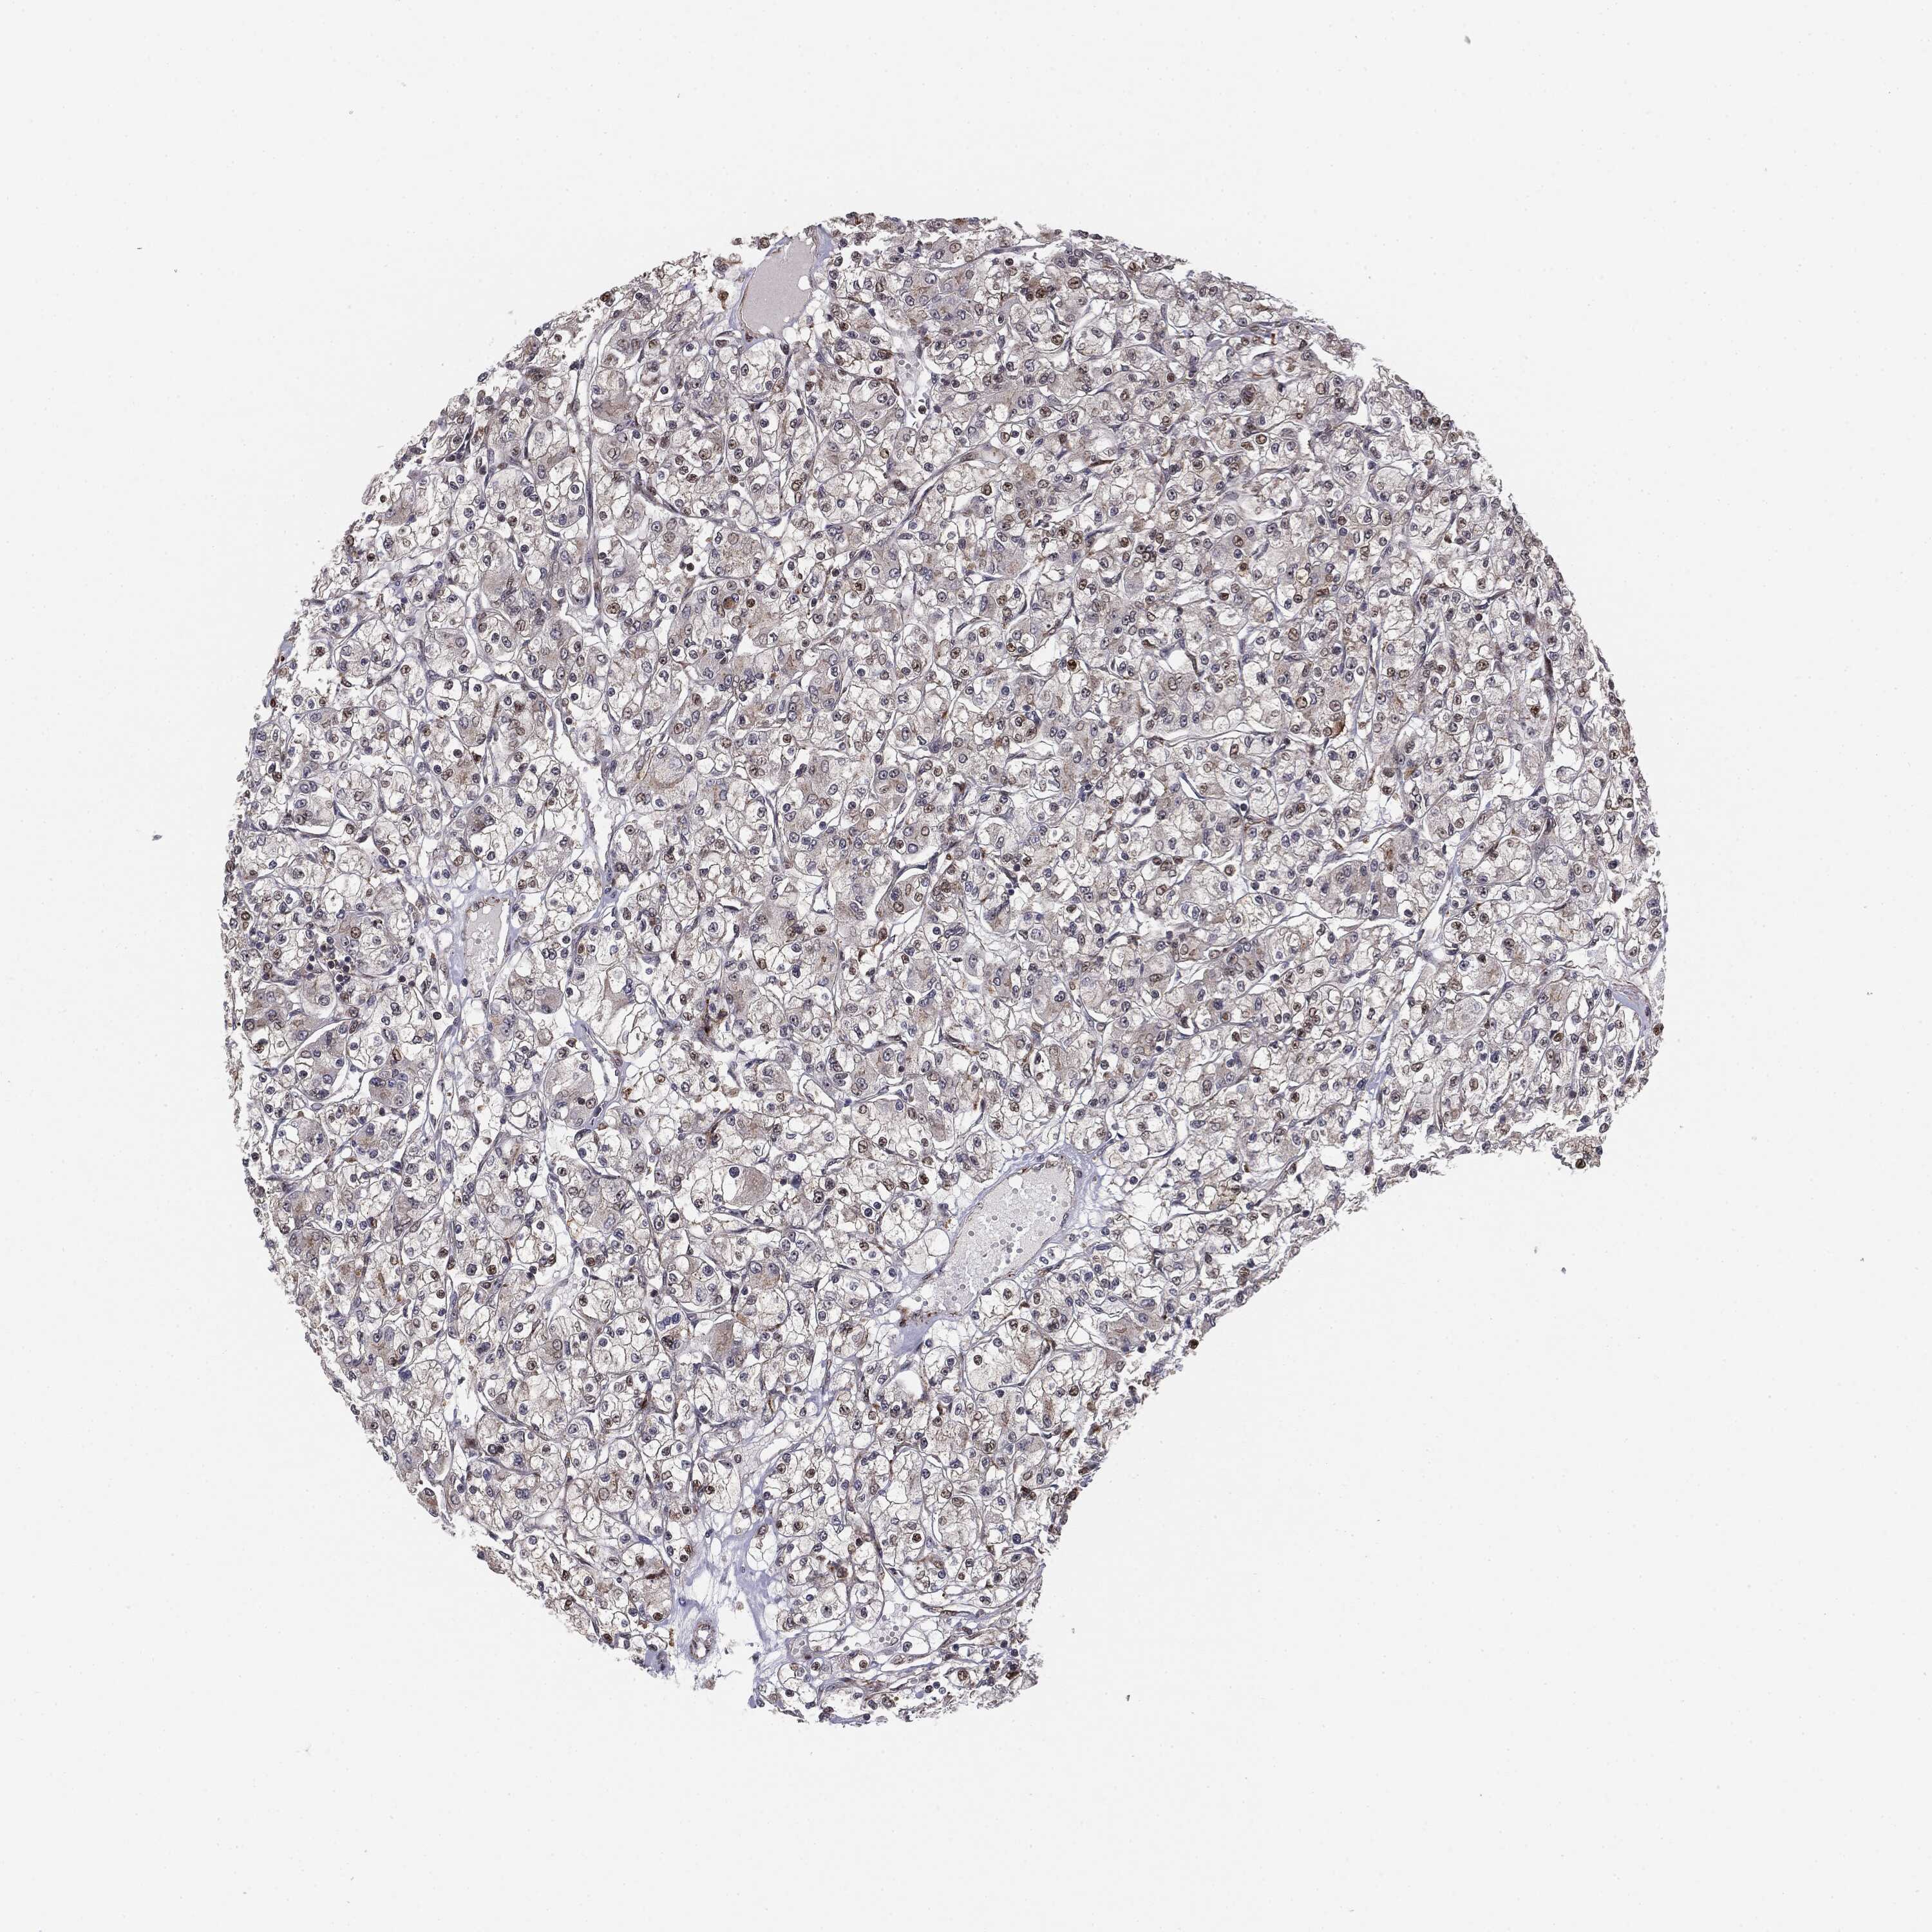

KIDNEY RENAL CLEAR CELL CARCINOMA (TCGA) - Interactive survival scatter ploti

The Survival Scatter plot shows the clinical status (i.e. dead or alive) for all individuals in the patient cohort, based on the same data that underlies the corresponding Kaplan-Meier plots. Patients that are alive at last time for follow-up are shown in blue and patients who have died during the study are shown in red.

The x-axis shows the expression levels (FPKM) of the investigated gene in the tumor tissue at the time of diagnosis. The y-axis shows the follow-up time after diagnosis (years). Both axes are complimented with kernel density curves demonstrating the data density over the axes. The top density plot shows the expression levels (FPKM) distribution among dead (red) and alive patients (blue). The right density plot shows the data density of the survived years of dead patients with high and low expression levels respectively, stratified using the cutoff indicated by the vertical dashed line through the Survival Scatter plot. This cutoff is automatically defined based on the FPKM cutoff that minimizes the p-score. The cutoff can be changed by dragging the vertical line or by entering a cutoff value in the square labeled "Current cut-off".

Under the Survival Scatter plot the p-score landscape (black curve; left axis) is shown together with dead median separation (red curve; right axis). Dead median separation is the difference in median mRNA expression between patients who have died with high and low expression, respectively. It is calculated as follows: median FPKM expression of dead patients with high expression - median FPKM expression of dead patients with low expression. This is intended to aid the user in visually exploring custom cutoffs and the associated p-scores and dead median separation.

Individual patient data is displayed and can be filtered by clicking on one or more of the category buttons on the top of the page. Categories describing expression level and patient information include: high, low, alive, dead, female, male and tumor stages. The scale of the x-axis can be toggled between linear and log-scale by clicking on the "x log" button. Mouse-over function shows TCGA ID, patient information and mRNA expression (FPKM) for each patient.

& Survival analysisi

Kaplan-Meier plots summarize results from analysis of correlation between mRNA expression level and patient survival. Patients were divided based on level of expression into one of the two groups "low" (under cut off) or "high" (over cut off). X-axis shows time for survival (years) and y-axis shows the probability of survival, where 1.0 corresponds to 100 percent.

PTEN is not prognostic in Kidney Renal Clear Cell Carcinoma (TCGA)

Best expression cut offi

Based on the FPKM value of each gene, patients were classified into two groups and association between prognosis (survival) and gene expression (FPKM) was examined. The best expression cut-off refers the FPKM value that yields maximal difference with regard to survival between the two groups at the lowest log-rank P-value. Best expression cut-off was selected based on survival analysis .

When clicking on this number, the vertical dashed line indicating cut-off, the interactive survival plot, and the Kaplan-Meier curve will be adjusted to show results based on the best expression cut-off.

: 20.55

TCGA RNA samplesi

RNA-seq data is reported as average FPKM (number Fragments Per Kilobase of exon per Million reads), generated by the The Cancer Genome Atlas (TCGA) .

Normal distribution across the dataset is visualized with box plots, shown as median and 25th and 75th percentiles. Points are displayed as outliers if they are above or below 1.5 times the interquartile range. FPKM values of the individual samples are presented next to the box plot.

Average pTPM 24.3

Number of samples 521